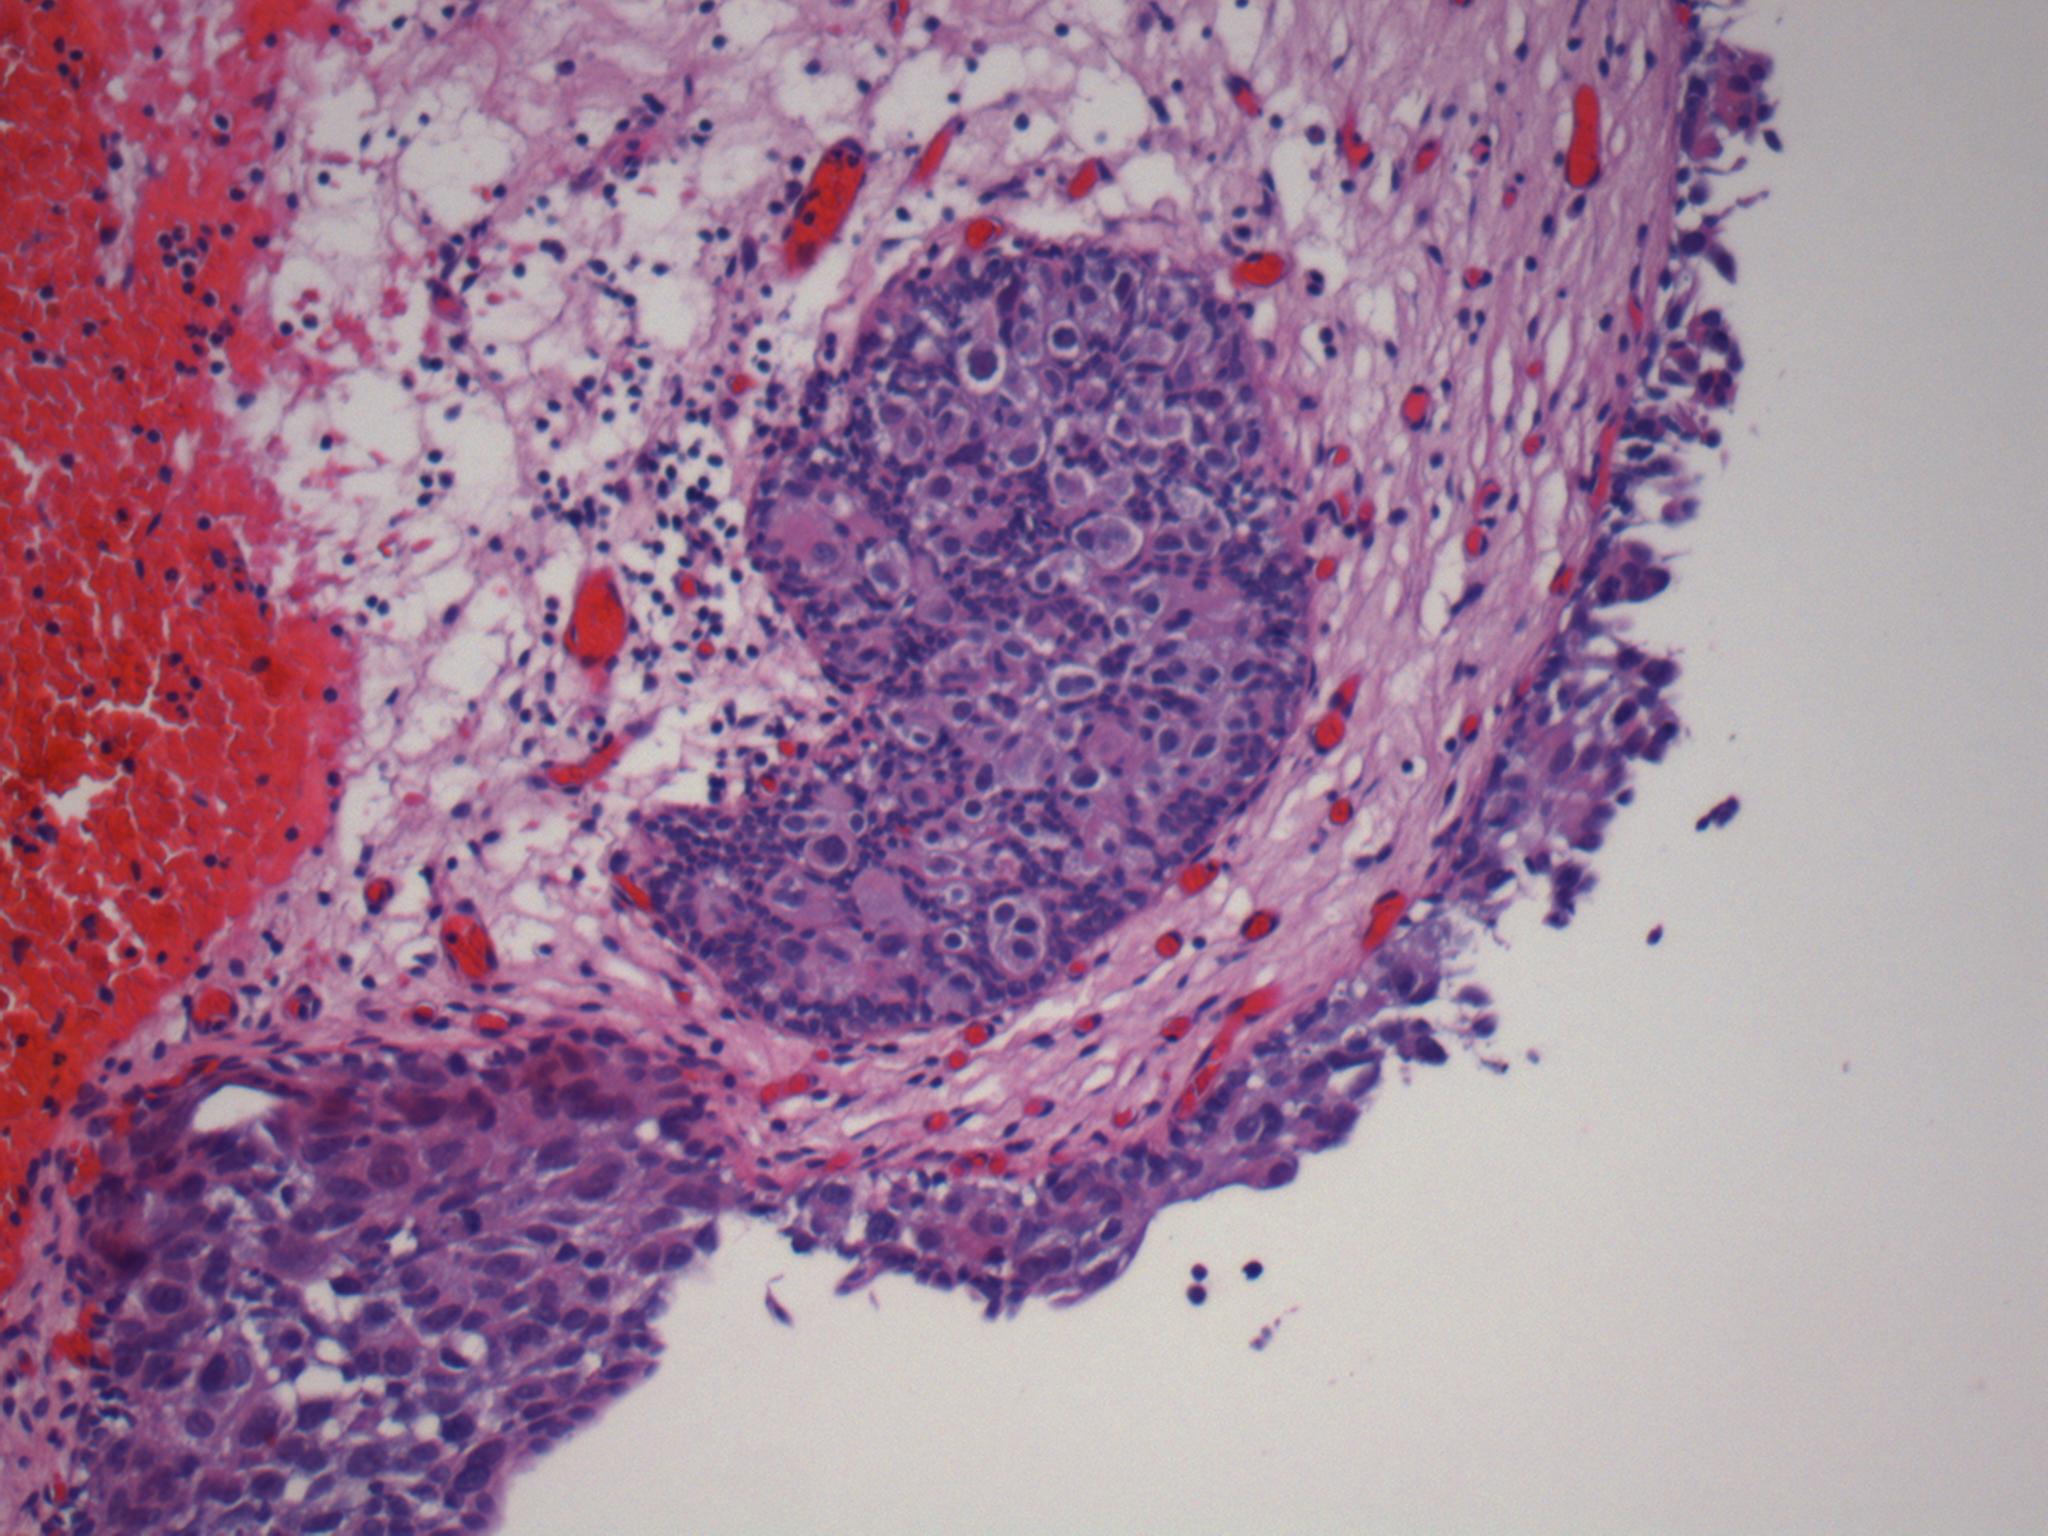

Consensus grade: Carcinoma in situ (CIS)

Pagetoid spread into von Brunn's nest |

partially pagetoid |

pagetoid |

Case description (by case creator):

Pagetoid involvement of von Brunn nests by malignant cells. The surface urothelium displays loss of cohesion